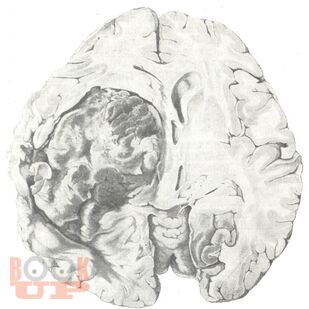

В представленном учебном пособии в виде краткого реферата во введении описано место опухолей головного мозга среди заболеваний у детей, их частота и локализация. Подробно описываются структурно-биологические свойства опухолей головного мозга (астроцитомы, глиобластомы, олигоденд-роглиомы, эпендимомы, менингиомы, краниофарингиомы, сосудистые опухоли, саркомы). Достаточно полно представлены клиника и диагностика опухолей мозга у детей, их особенности в зависимости от пола и возраста ребенка. В кратком заключении описываются затронутые вопросы. Весьма ценными являются вопросы для самоконтроля и тестовые задания. В указателе литературы даны основные источники, в том числе монографии самих авторов.